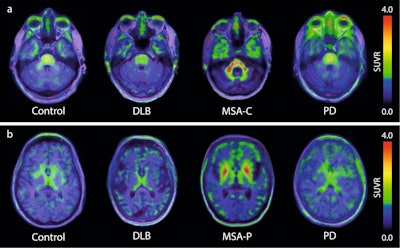

(a) Transversal images at the level of the middle cerebellar peduncles in a control participant, and patients with dementia with Lewy bodies (DLB), multiple system atrophy-cerebellar subtype (MSA-C), and Parkinson’s disease (PD). (b) Transversal images at the level of the basal ganglia in a control participant, and patients with DLB, MSA-parkinsonian type. SUVR images for (a, b) have been created using the occipital cortex as a reference region. Image courtesy of Nature Communications.

In this study, Hansson and colleagues performed F-18 ACI-12589 PET imaging in 23 participants with a-synuclein related disorders, 11 with other neurodegenerative disorders, and eight controls. The analysis revealed that F-18 ACI-12589 demonstrated clear binding in the cerebellar white matter and middle cerebellar peduncles of MSA patients, regions known to be highly affected by a-synuclein pathology.